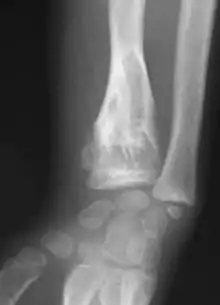

X-ray image showing enchondromas localized in the lower part of the radius of a 7-year-old girl with Ollier disease. | |

Abnormal bone growth such as shortening or thickening and deformity may be observed in patients of Ollier disease. These bone lesions are visible at birth using radiography but are usually not screened or examined for until clinical manifestations present during early childhood. However, some patients may exhibit no signs of any symptoms.[1] One study found thirteen to be the mean age of diagnosis in patients with Ollier disease. In an X-ray, there would normally be the presence of several homogeneous lesions of an oval or elongated shape with bone edges that are slightly thickened.[3] With age, these lesions may calcify and appear as diffusely minute spots or stippled. Fan-like septations or streaks would be indicative of the presence of several enchondromas. Early detection and consistent and repeated monitoring is important in order to prevent and treat any potential bone neoplasms.